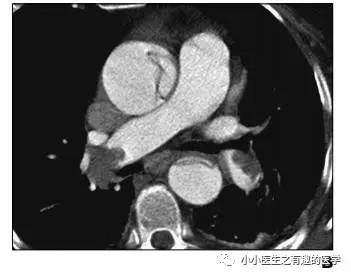

作者单位:Department of Radiology, University of Washington MedicalCenter, University of Washington School of Medicine。华盛顿医科大学。

翠花上菜,学者上图。

发现嫌疑犯,立即逮捕。

增强CT对比,一目了然。

上面的病人,增强CT放大了。

下面是另外一个:

星号的地方。